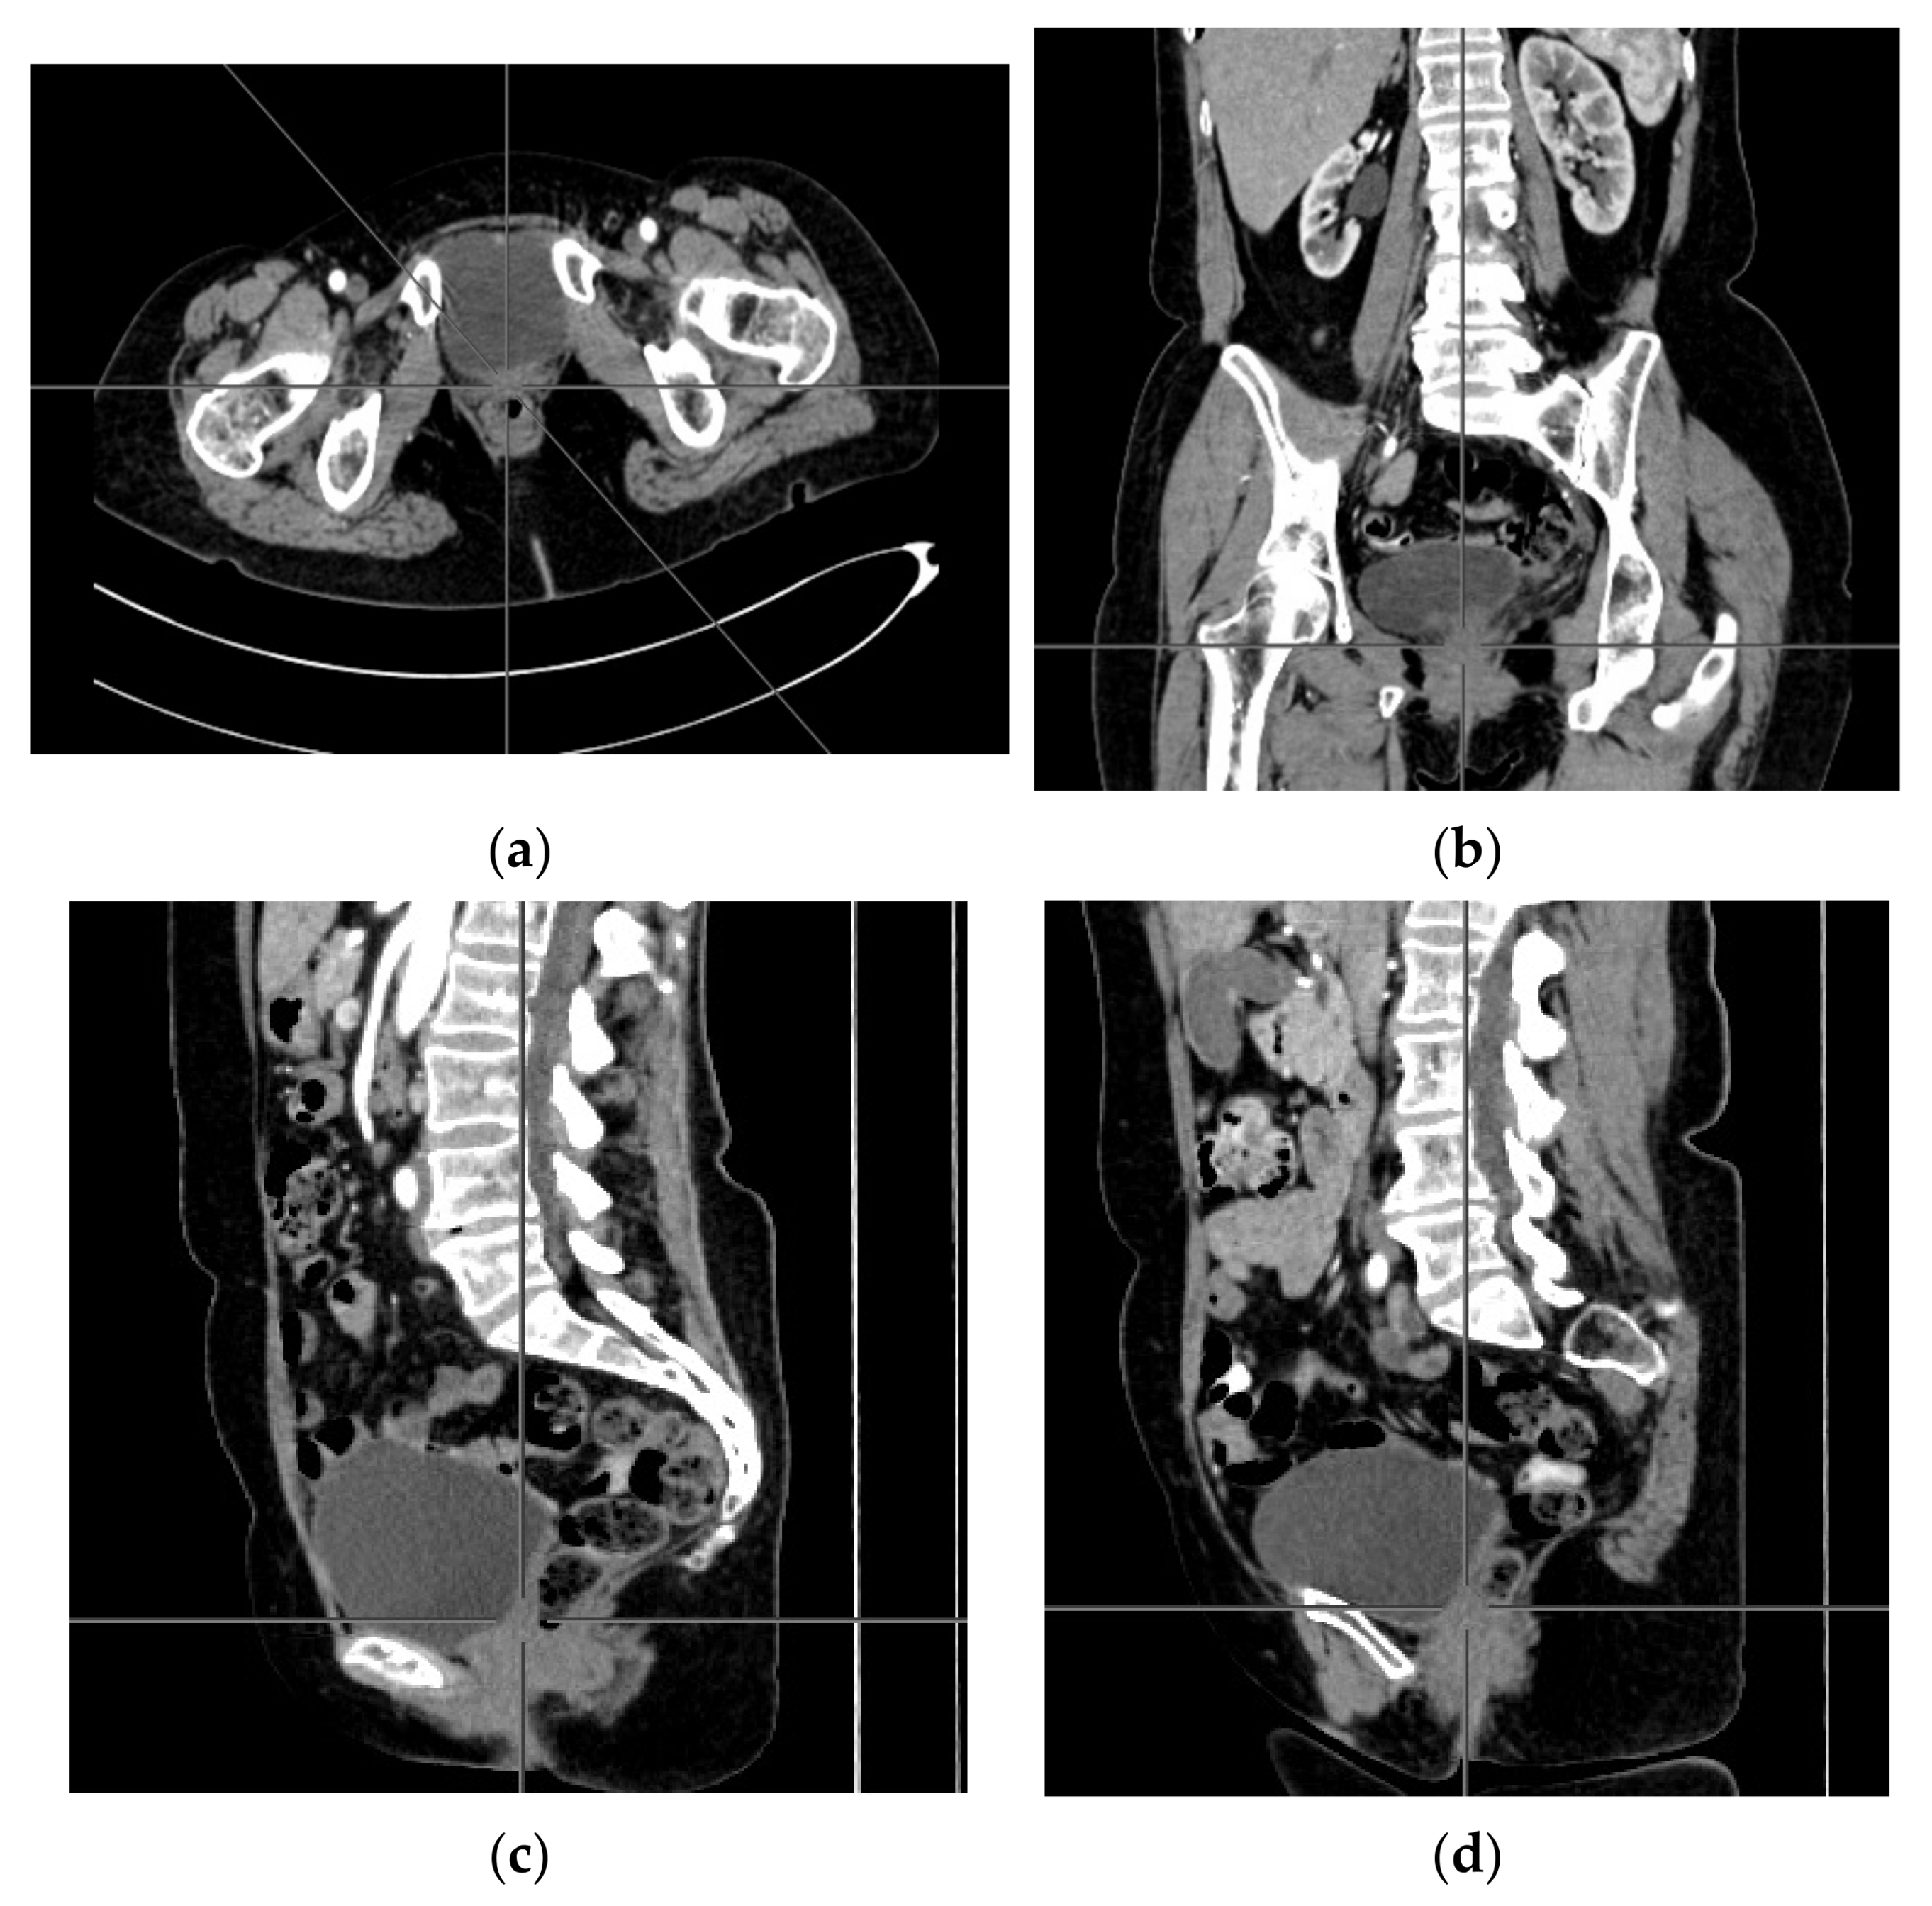

A computer tomography of the abdomen and pelvis was also performed every 3 months for the possible detection of ovarian cancer recurrence. No CT changes suggestive of recurrence were observed in the patient during the treatment. There are illustrates scans on the same section from CT performed at the beginning of PARP inhibitor treatment (Figure 2) and before 48 cycle of olaparib chemotherapy (Figure 3).

Figure 2. (ad) CT scans performed at the beginning of olaparib treatment.